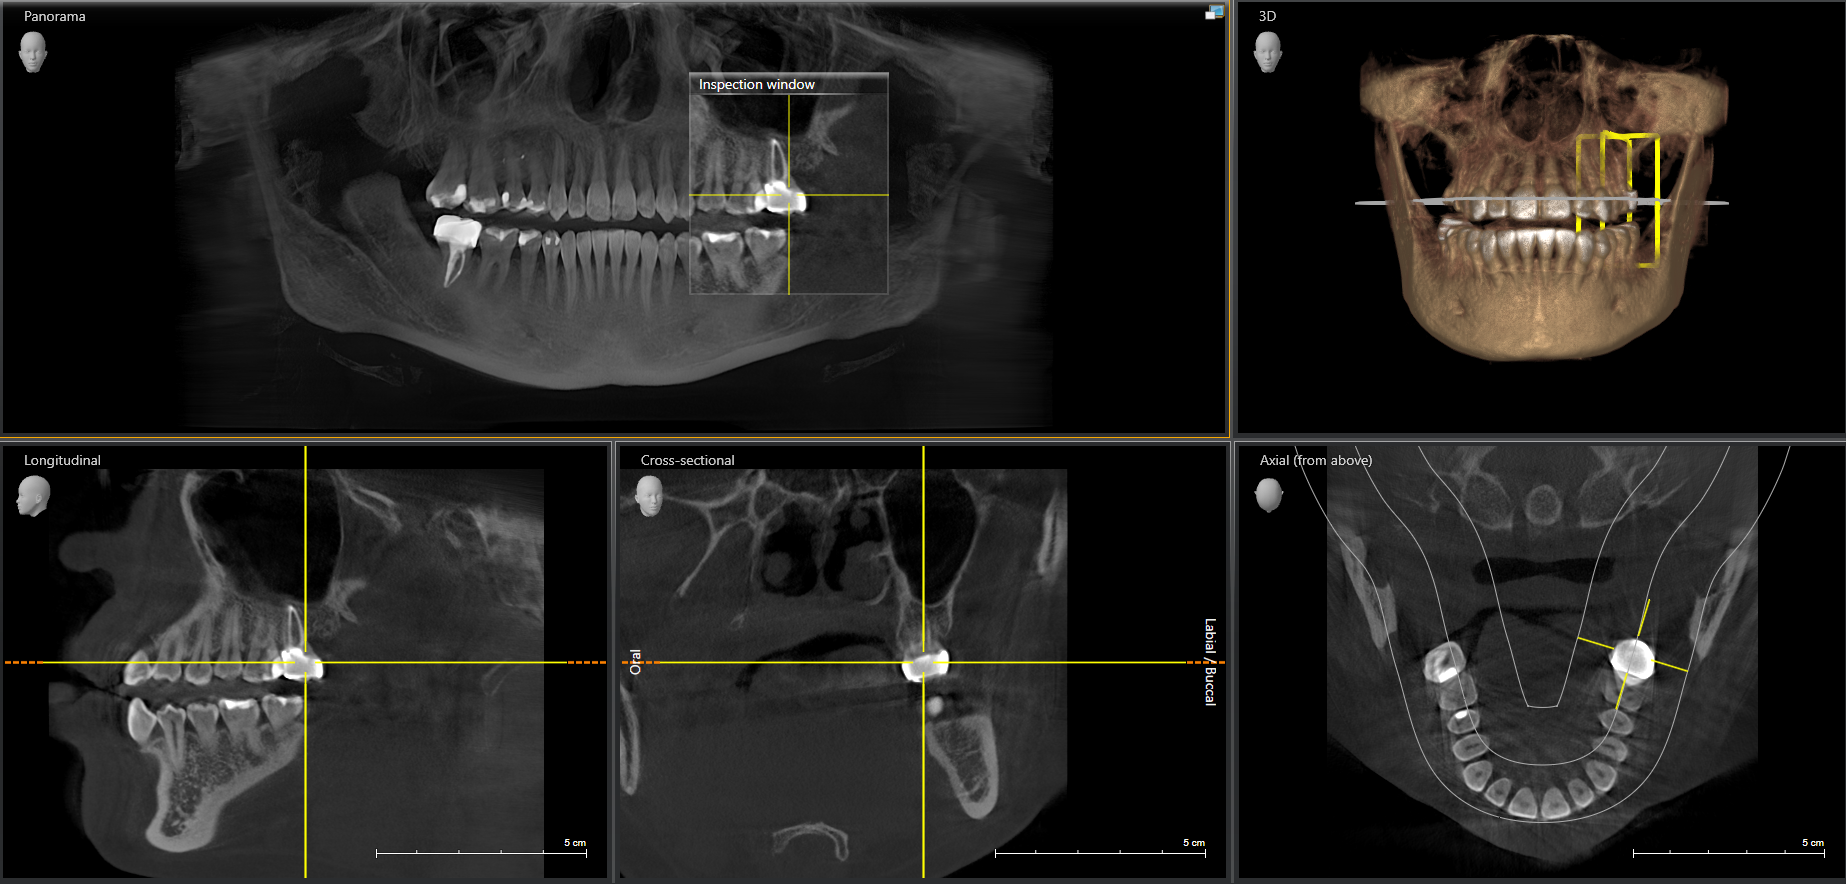

We use cutting-edge ceramic implant technology for superior biocompatibility.